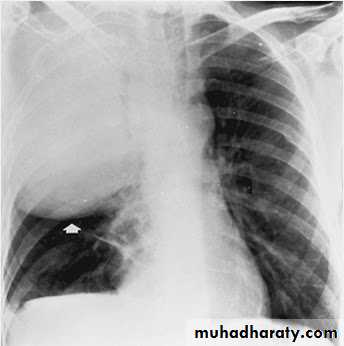

Plain film

The classical appearance of a pulmonary abscess is a cavity containing an air-fluid level. In general abscesses are round in shape, and appear similar in both frontal and lateral projections.

Very important

Empyema vs pulmonary abscess1.relationship to adjacent bronchi / vessels

abscesses will abruptly interrupt bronchovascular structures

empyema will usually distort and compress adjacent lung

2.split pleura sign thickening and separation of visceral and parietal pleura is a sign of empyema

3.abscesses have thick irregular walls

empyema are usually smoother

4.angle with pleura

abscesses usually have an acute angle (claw sign)

empyema have obtuse angles